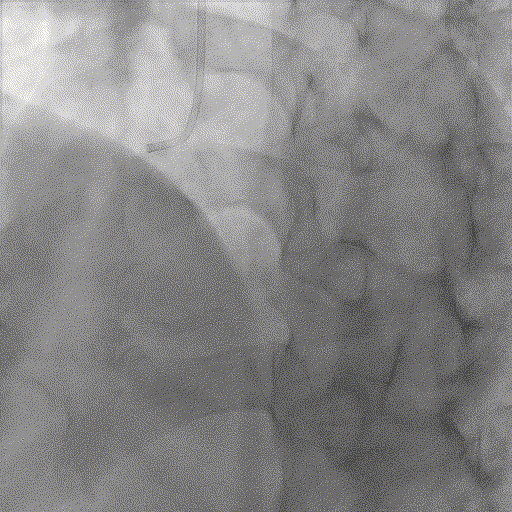

基础造影

右冠状动脉近段基本正常,中段狭窄50%,远段原支架通畅,右冠-后降支开口狭窄70%;左主干狭窄40%;前降支近中段全程弥漫性钙化病变,狭窄80-99%,第一对角支狭窄60%,第二对角支狭窄80%;回旋支近段基本正常,远段狭窄60%。

手术经过

导丝到位

当指引导管冠脉开口到位后,选择三根对应导丝分别送入LAD、D1、D2远端。

球囊预扩

选择不同尺寸的预扩球囊逐级预扩张病变,复查造影狭窄减轻不明显。为了解血管真实情况,遂启用IVUS检查。